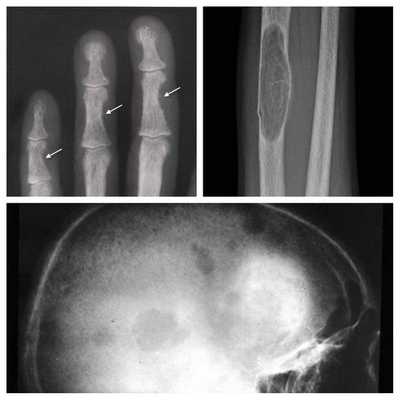

Длительное течение заболевания сказывается на формировании костей. Так, н а поздних стадиях вовремя не диагностированного гиперпаратиреоза наблюдаются:

- разрушение дистальных или концевых фаланг конечностей;

- сужение дистального отдела ключиц;

- очаги разрушения костей черепа;

- бурые опухоли длинных костей.

- Рентгенография. При денситометрии обнаруживается уменьшение плотности костной ткани, субпериостальная резорбция на концевых, средних и основных фалангах кистей. Концевые фаланги часто фестончатые, кружевные. Рентгенография почек выявляет признаки нефрокальциноза (кальцификаты).